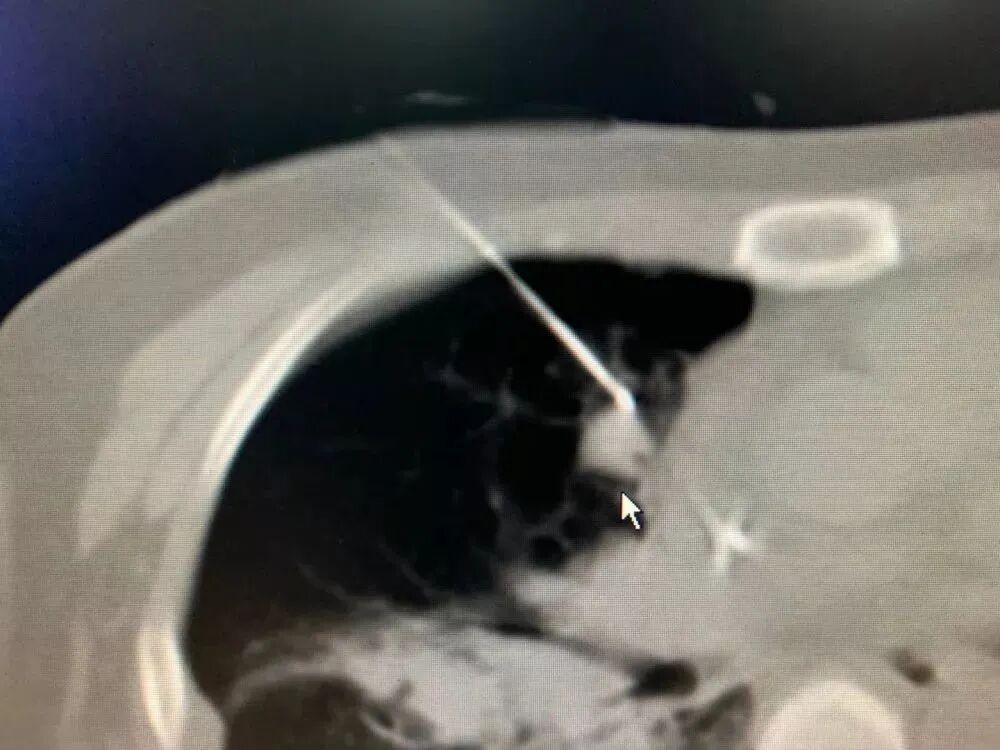

之前有一位腸癌患者,經(jīng)歷手術(shù)和放化療后,發(fā)生了肺轉(zhuǎn)移。腫瘤雖然不大,卻長在了心臟旁邊。如果直接開刀,風(fēng)險極高;直接做冷凍消融,又可能誤傷心臟。最終我們決定采用“釣魚執(zhí)法”冷凍消融術(shù)。

手術(shù)中,我用一根冷凍針“釣”住腫瘤,像收起魚線那樣,慢慢把它從心臟附近牽引到更安全的位置,再實施冷凍消融。整個過程必須極度謹(jǐn)慎,因為心臟周圍血管豐富,稍有不慎就可能引發(fā)大出血。

類似的情況還包括長在肺門附近的結(jié)節(jié),位置也非常棘手。借助冷凍固定和“釣魚”技巧,使結(jié)節(jié)遠離肺門大血管,再插入活檢針和冷凍針,就能安全、徹底地消滅它。